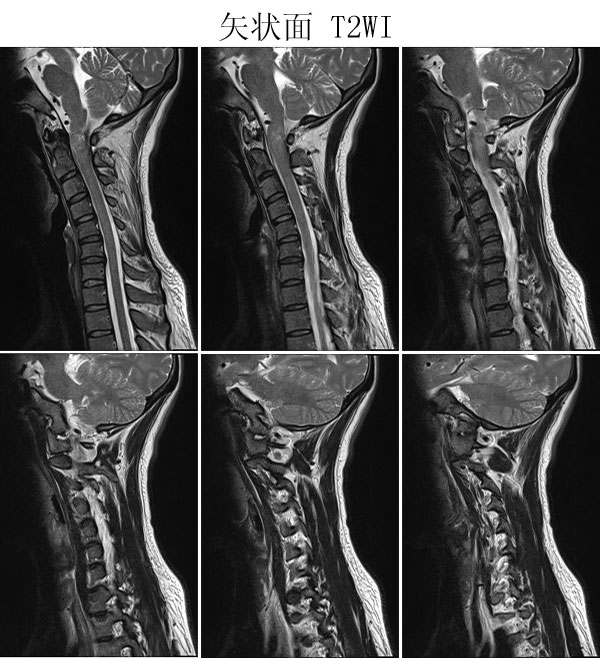

神经鞘瘤

本病例来自广东同江医院

病史:女,27岁,洗头按摩时扭颈导致昏迷,检查发现颈椎占位

手术病理: